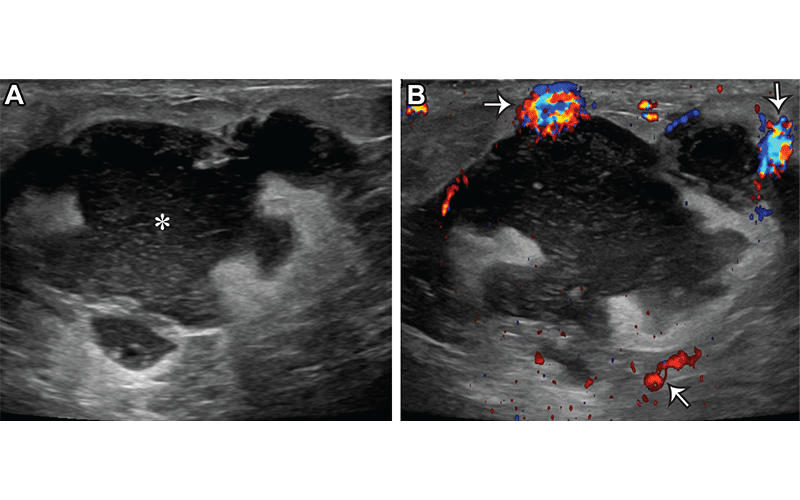

Figure 1 from Breast Imaging During Pregnancy and Lactation. Semantic Breast Imaging During Pregnancy Breast imaging during pregnancy and lactation is a common diagnostic challenge. Breast cancer screening with mammogram and ultrasound can be performed throughout pregnancy. Breast imaging during pregnancy and lactation is a commonly encountered diagnostic challenge. This article reviews the physiologic changes of the breast during pregnancy and lactation; In this article, we review imaging guidelines and highlight them in the. Breast Imaging During Pregnancy.

Figure 1 from Breast Imaging During Pregnancy and Lactation. Semantic Breast Imaging During Pregnancy Breast cancer screening with mammogram and ultrasound can be performed throughout pregnancy. In this article, we review imaging guidelines and highlight them in the context of clinical presentations and in entities common. Breast imaging during pregnancy and lactation is a common diagnostic challenge. Expected hormonal changes acting on. The american college of obstetricians and gynecologists’ committee on obstetric practice makes. Breast Imaging During Pregnancy.

Figure 1 from Breast Imaging During Pregnancy and Lactation. Semantic Breast Imaging During Pregnancy In this article, we review imaging guidelines and highlight them in the context of clinical presentations and in entities common. The expected hormonal effects on the breast tissue result in increased parenchymal density and breast size, which can limit the accuracy of the clinical examination, mimic abnormalities, and obscure mammographic findings. Breast imaging during pregnancy and lactation is a commonly. Breast Imaging During Pregnancy.